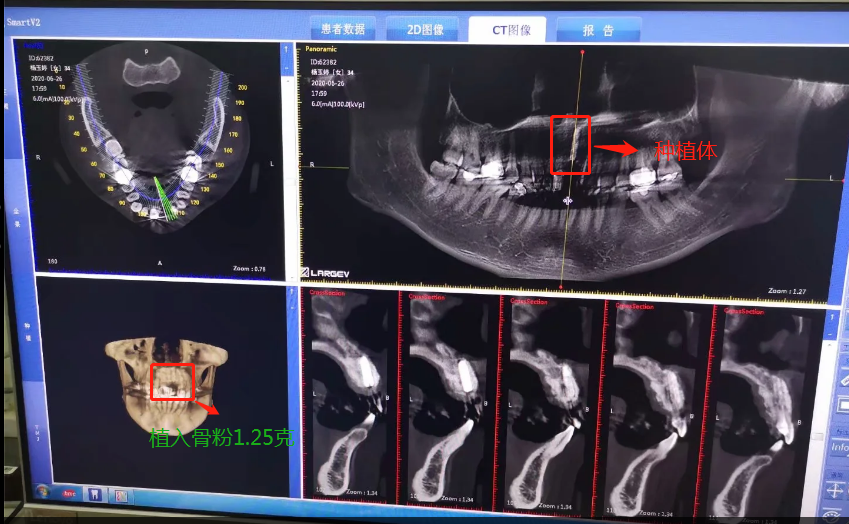

第二次做完植入手術(shù)后拍的CT

2020年6月26日,終于等到了,我要種植了牙根啦,我牙根弄了法國安卓建品牌的種植體,之前還去幾家口腔門診和烈士陵園的光華口腔也咨詢過和對比價(jià)格,瑞士ITI品牌太貴了(還有別的品牌M美國皓圣、韓國登騰、德國ICX、瑞典諾貝爾等),本來選美國皓圣,但我的是門牙,要選材質(zhì)比較好,考慮美觀問題,后選擇中等價(jià)位的安卓健。手術(shù)很快,而且傷口不是很大,我四天就康復(fù),做完當(dāng)下就可以說話,完全沒有阻礙。因?yàn)檠栏N進(jìn)去必須要等半年時(shí)間跟我骨頭長在一起,因?yàn)槲耶?dāng)時(shí)做手術(shù)的時(shí)候種植入的骨粉還是軟的,還沒有變成硬骨頭?,F(xiàn)在的階段是等待上基臺,上完基臺半個(gè)月時(shí)間上牙冠。2020年12月26日上基臺。預(yù)計(jì)要2021年1月份可以全部完成種牙過程,期待著我?guī)涎例X的那一刻。

植入種植體后拍的CT